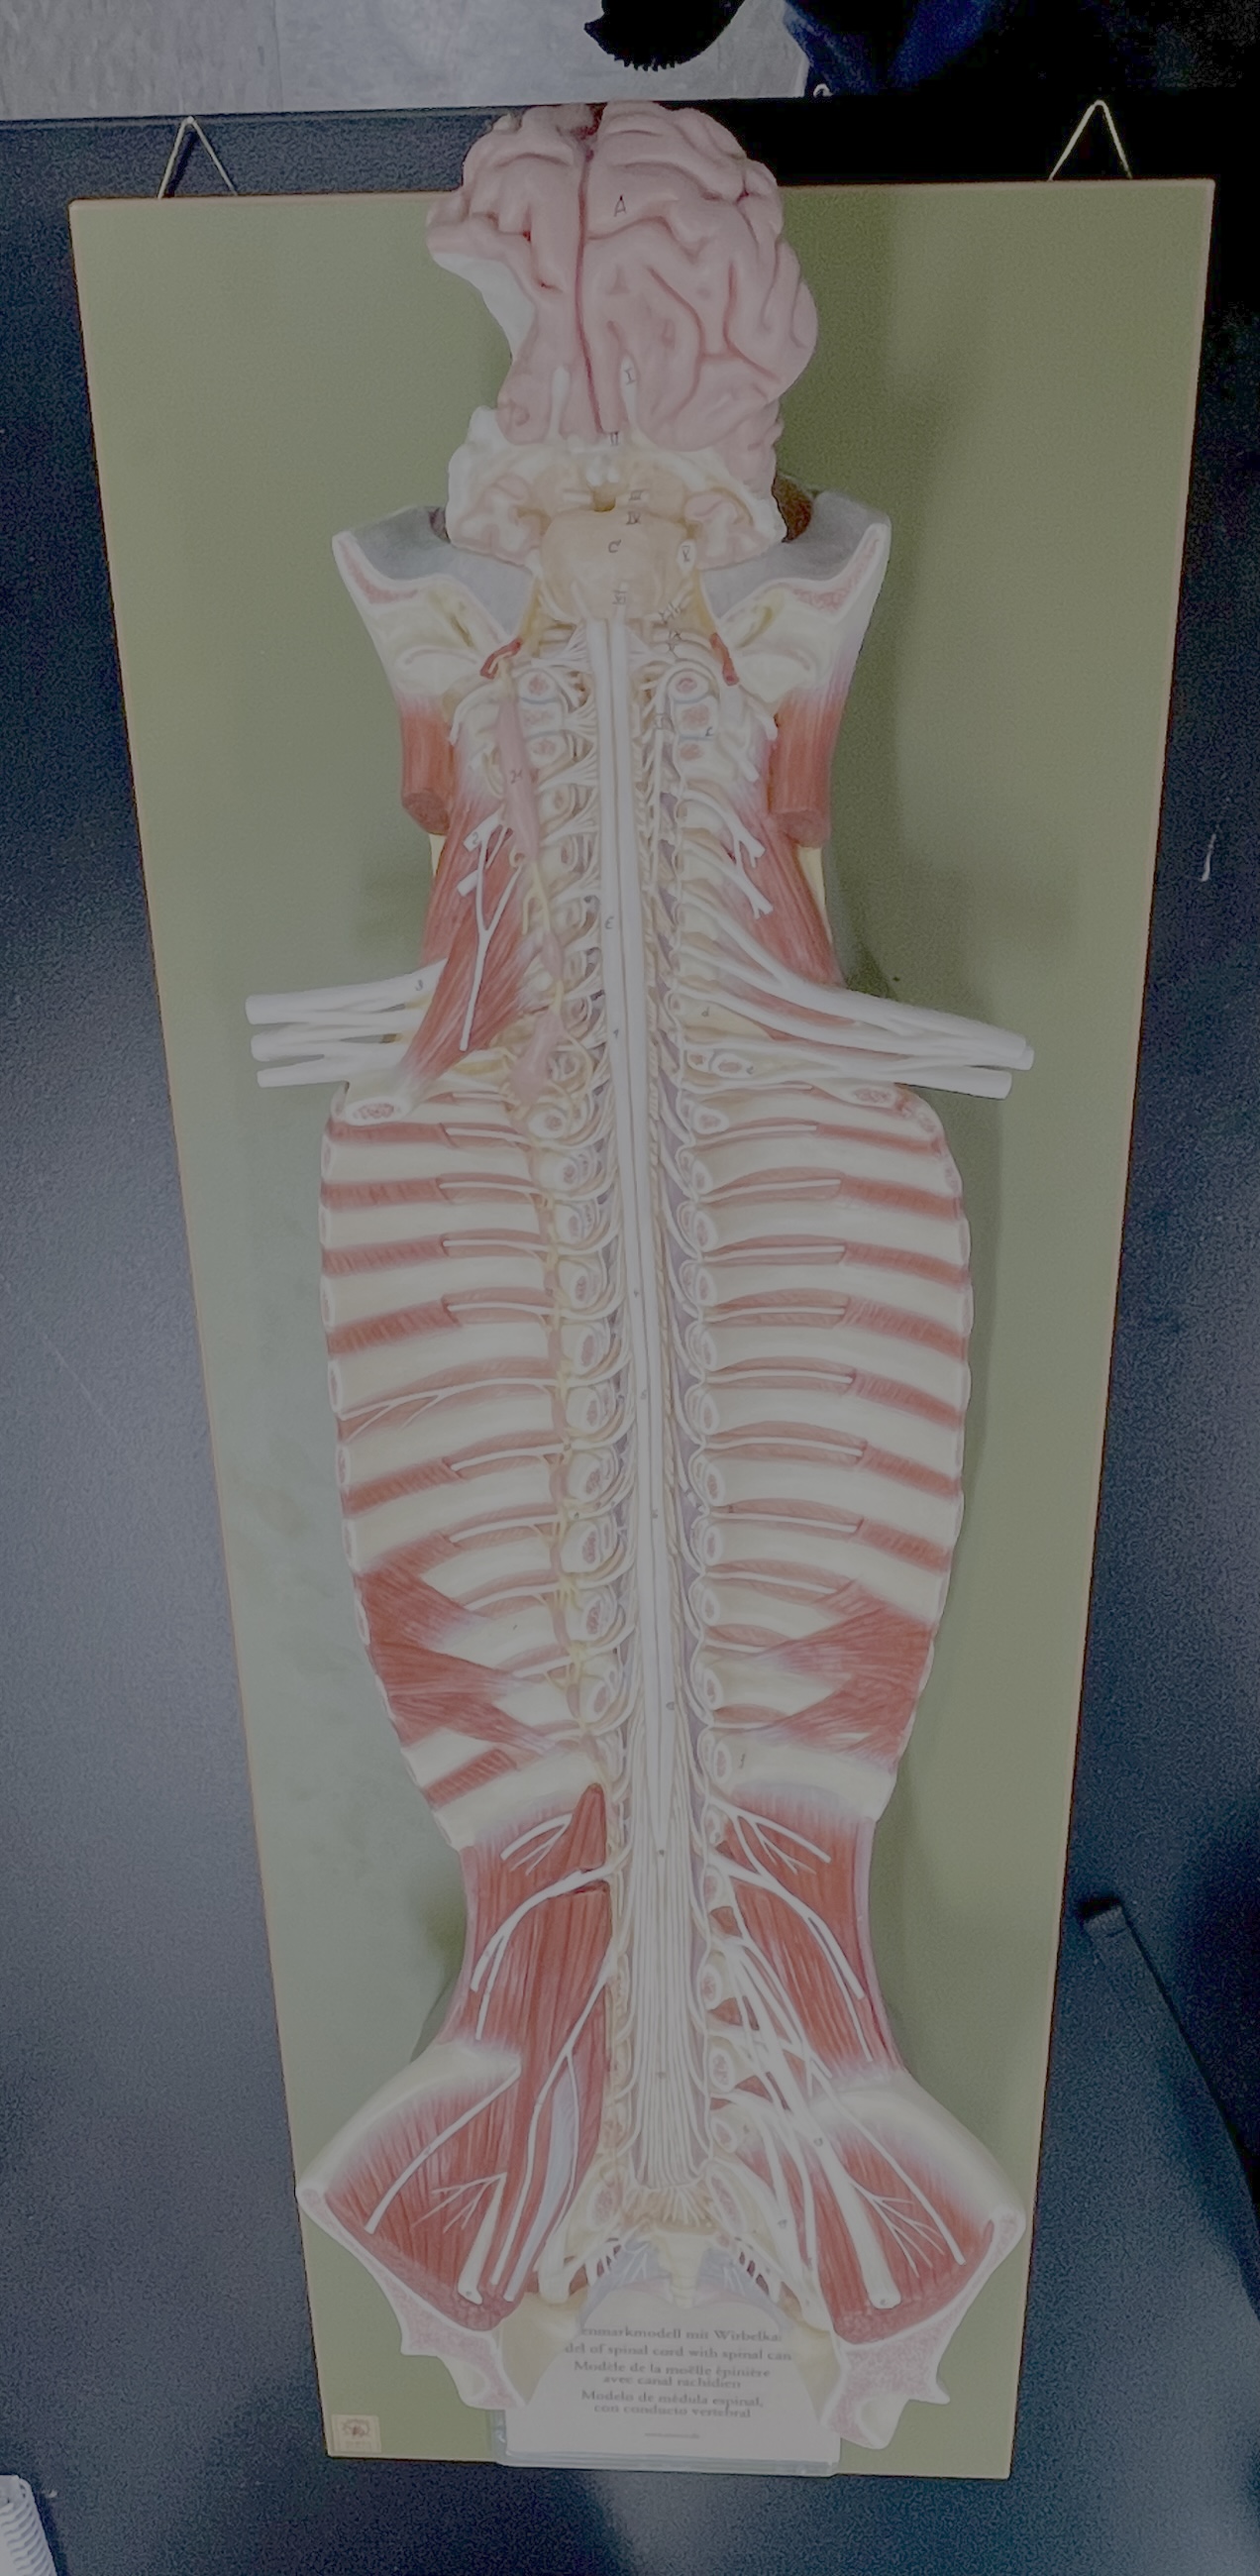

What type of spinal nerve is this? How many pairs?

cervical (8 pairs)

What type of spinal nerve is this? How many pairs?

thoracic (12 pairs)

What type of spinal nerve is this? How many pairs?

lumbar (5 pairs)

What type of spinal nerve is this? How many pairs?

sacral (5 pairs)

What type of spinal nerve is this? How many pairs? (not pictured)

coccygeal (1 pair)

cervical enlargement

cervical enlargement

thoracic segment

lumbar enlargement

lumbar enlargement

conus medullaris

conus medullaris

filum terminale

cauda equina

sympathetic chain ganglia

cervical plexus – phrenic nerve

cervical plexus – phrenic nerve

brachial plexus – ulnar nerve

brachial plexus – median nerve

brachial plexus – radial nerve

lumbar plexus – femoral nerve

lumbar plexus - femoral nerve

sacral plexus – sciatic nerve

sacral plexus – sciatic nerve